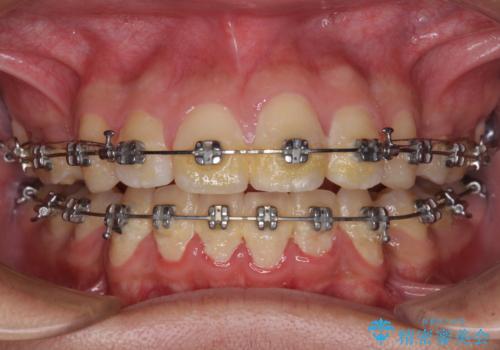

- メタルブラケット

- 2年10ヶ月

- 10-30回

小学生の頃に上顎前歯をぶつけ、歯の一部が破損している状態であったので、歯根が歯槽骨と癒着して移動しない可能性がありましたが、無事に治療を終えることができました。

受験勉強と重なり、舌のトレーニングが十分に行えず、高校生としてはやや長期間の治療となりました。